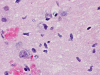

The patient was a 5 year-old Vietnamese boy who presented with the chief complaints of headaches, vomiting, and ataxia.  CT scan revealed a pineal tumor with small calcifications and hydrocephalus (Panel 1).  On MRI, the mass is a well demarcated midline mass involving the pineal area. There is also heterogeneous enhancement and cystic component (Panel 2 and 3).